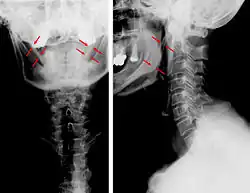

| Anteroposterior and lateral radiographs of cervical spine showing ossification of the stylohyoid ligament on both sides | |

CT scan, coronal section showing bilateral extended styloid process and stylohyoid ligament ossification (incidental finding) -